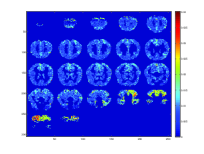

In Figure 4, we display 4 such groups of brain regions that are activated given a stimulus of a group of similar words; these words can be seen in Table 2, along with groups of similar questions that were highly correlated with the words of each group. Moreover, we were able to successfully identify high activation of the premotor cortex in Group 3, which is associated with concepts such as holding or picking items up.

Refer to caption

(a) Group 1

(b) Group 2

(c) Group 3

(d) Group 4

Figure 4: The latent brain images for the 4 word/question groups as shown in Table 2. We can see that for each different group, the activation pattern of certain brain regions is different. For instance, Group 3 refers to small items that can be held in one hand,such as a tomato or a glass, and the activation pattern is very different from the one of Group 1, which mostly refers to insects, such as bee or beetle. Additionally, Group 3, for instance, shows high activation in the premotor cortex which is associated with the concepts of that group.